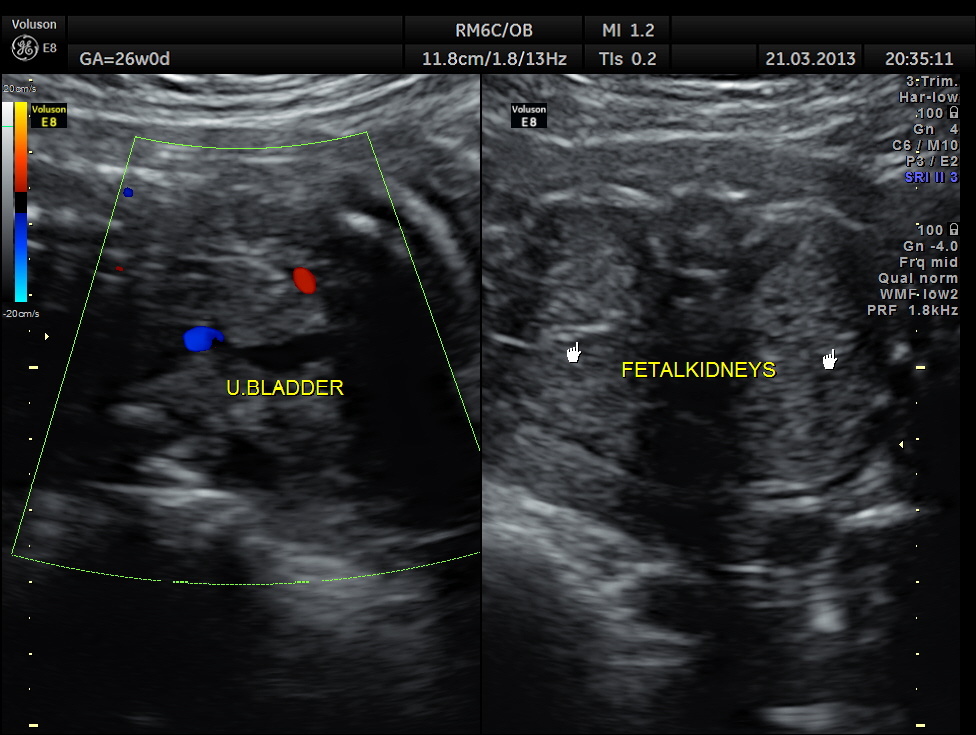

https://kriznanultrasoundimages.com/2013/05/12/tetralogy-of-fallot-tof/ at this time there was a revision of the cardiac findings : LEFT ATRIAL ISOMERISM WITH TETRALOGY OF FALLOT The irregular rhythm was not made out now. Apart from this the foetus has symmetrical IUGR and oligohydramnios Now the child was brought when she was 51 days old . She was born prematurely at 33 weeks of gestation . She had been seen at three higher institutions . The paediatric cardiologist has given a working diagnosis of CONO TRUNCAL VSD. But the catch was that the child had renal dysfunction with s .creatinine around 2 mgms and the ultrasound could not visualise the left kidney. The right kidney was reported to be hyperechoic . The following 2 pictures were of the fetal kidneys , as seen during the scan earlier.